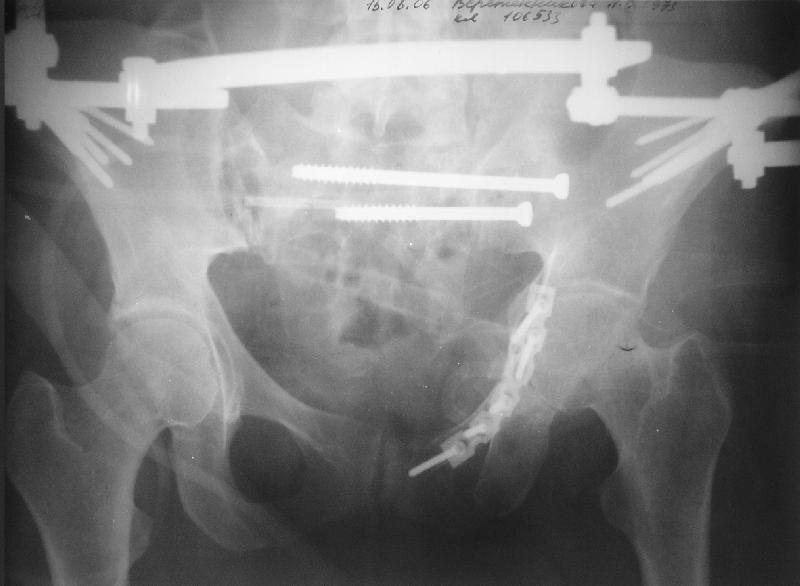

Прооперировали молодую девушку 32 лет спустя 9 мес после травмы. Имелся стойкий болевой синдром, неопороспособность левой н/конечности, моторные и сенсорные нарушения в левой голени и стопе, патологическая подвижность левой половины таза. Первым этапом закрыто в аппарате исправили деформацию ( в течении 2,5 нед). Вторым закрытое введение илиосакральных винтов в крестец (канюллированные 7,2 мм Chm) + туннелизация зоны псевдоартроза спицама Киршнера, реконструкция передних отделов таза, накостный остеосинтез . Аппарат частично демонтирпован, оставлена "передняя рама" После устранения деформации отмечен регресс неврологической симптоматики, уменьшение болевого синдрома. Интересующие вопросы: 1. Прогноз для сращения псевдоартроза крестца. 2. сроки нагрузки весом левой половины таза. Буду очень признателен за ваши мнения по этому поводу.A female 32 y.o. admitted to our unit 9 months after initial injury with pain, inability to bear weight at the left lower limb, sensor and motor disturbances in the left foot and tibia, with mobility of the left hemipelvis.At first closed reduction was performed by an external fixator within 2,5 weeks. After correction her pain decreased and some neurological progress was achieved. Now two iliosacral screws 7,2 mm were inserted, and anterior lesion was fixed by a plate. External fixator was partially unmounted, only anterior frame left in place.Images attached.How would you evaluate chances of healing of the sacrum with the current position?When would you allow weight-bearing of the left leg?THX in advance.

Мне нравится ваша закрытая репозиция девятимесячного ложного сустава, не знаю насчет туннелизации, но шурупы в 7.2 это серёзная конструкция. При стабильной фиксации крестец должен срастись, только я бы держал передний фиксатор до шести недель, костыли, а полную нагрузку разрешить через 12 недель.